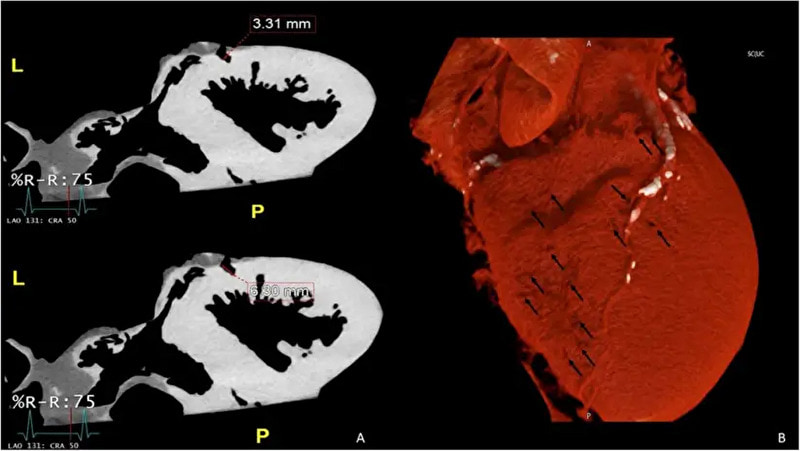

※ 画像